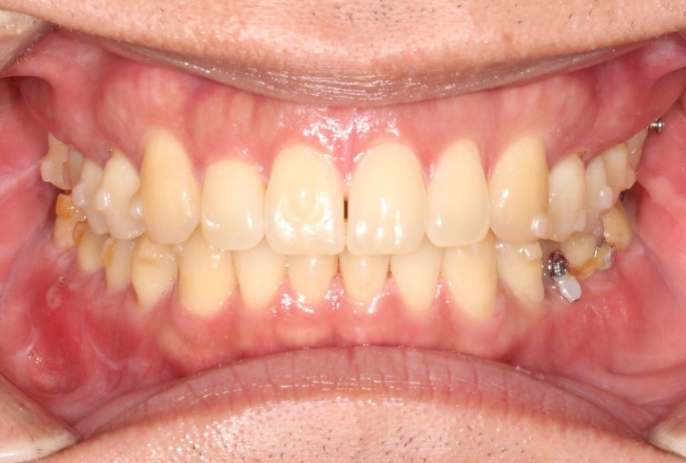

앞에서 보면 윗니가 아랫니를 많이 덮어서 앞니가 깊게 물리는 과개교합, 중심선 불일치,벌어진 앞니 등이 보입니다.

경미한 총생과 중심선 불일치, 가위교합, 벌어짐, 과개교합 문제가 있는 상황입니다.

인비절라인 라이트로 충분해서 인비절라인 라이트 권유드렸습니다.